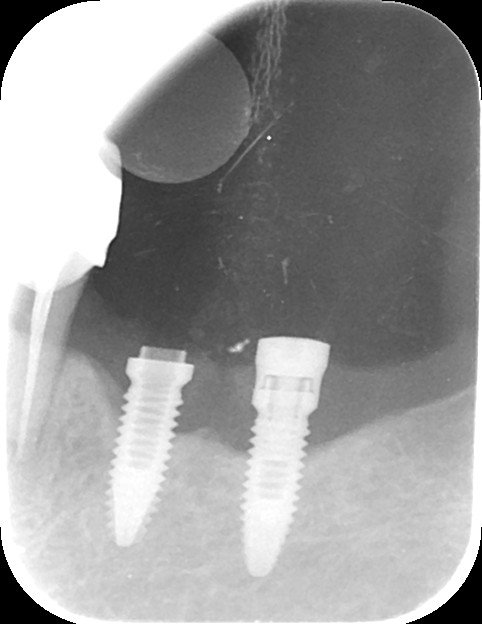

Buenos días. Estos casos que mando son de pacientes que vienen de una clínica que ha cerrado, y no se cuales son. Muchas gracias por su ayuda.